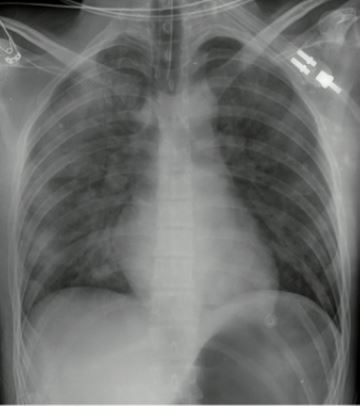

Se decidió buscar una posible etiología y descartar complicaciones, por lo que se tomó una tomografía axial computarizada de cráneo simple, en la cual no se observaron alteraciones, y una tomografía computarizada de alta resolución (TACAR) de tórax, donde se observó un patrón compatible con edema pulmonar ( figura 1). El paciente estaba en inminencia de falla ventilatoria, sin evidencia de defensa de vía área, por lo que se optó por iniciar medidas de soporte con ventilación mecánica invasiva (VMI) sin requerimiento de soporte vasoactivo.